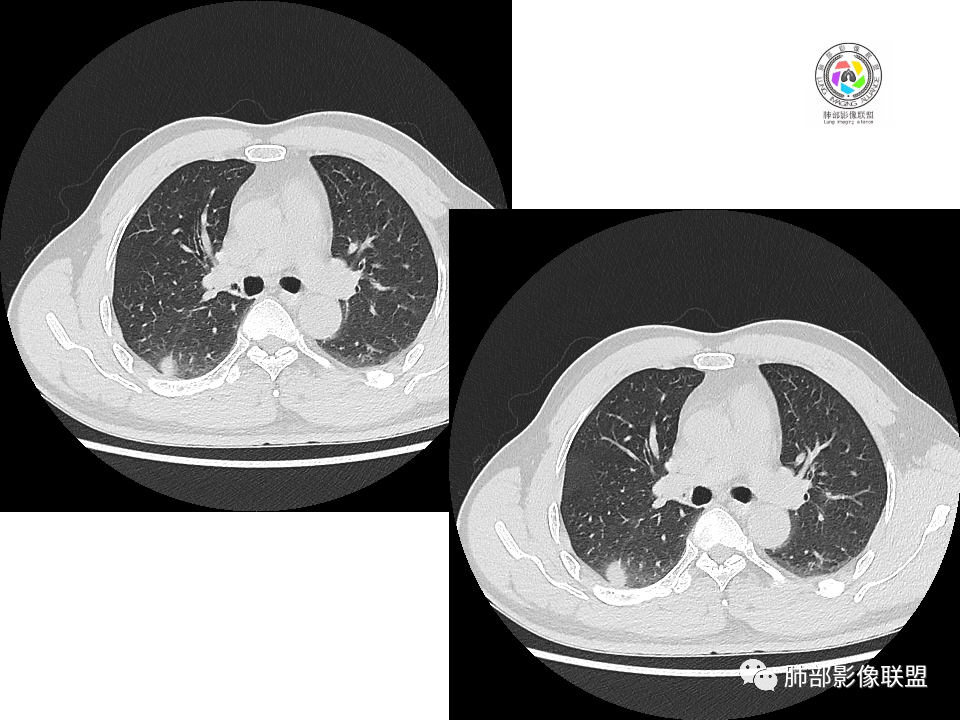

2.右肺下叶背段胸膜下块影,边界清楚光整,上下极见磨玻璃晕,未见明显分叶毛刺和棘状突起,未见胸膜凹陷或胸壁侵入。密度均匀,轻度不均匀强化。未见支气管进入。

3.右肺中叶外侧段胸膜下散在小片影,磨玻璃密度为主,边界不清,支气管相关。符合炎性特征!

4.右肺下叶基底段支气管血管束旁小结节影,边界清楚,强化不明显。注意,这结节在“遥远的”基底段。

5.慢性感染灶。缺乏临床表现,强化不显著会想到继发性肺结核,背段病灶过于光整均匀,周边过于干净使人狐疑,且“成掎角之势”的中叶病灶结核灶特点也着实不多。

有老师分析,多发病灶有磨玻璃晕,可以符合隐球菌感染,确实如此。但背段边缘如此锐利的块影还是更容易让人联想到新生物。

1、普通人隐球菌感染的时相:初期的隐球菌感染周围有晕,晕从多变少,或包裹,或吸收,结节实性区可迅速变大。后期(慢性期)的隐球菌周围无明显晕征,边界较清楚。

3、卫星灶与“蘑菇兄弟”:诊断隐球菌时,建议找卫星灶,卫星灶可以在遥远的地方。可以是遥远地方的微小结节——“小蘑菇兄弟”。有些远处的卫星灶,通常是不规则饱满实性的,晕征不明显。隐球菌的卫星灶非常“隐”,但发现率高达60%多,诊断价值高。

5、周围毛刺纤维、边缘形态等:坏死包裹会使得结节变圆;结节多缺乏明显的分叶征,缺乏局部突出生长能力;如果出现分叶,是由多处肉芽肿中心形成。没有坏死的局限化,结节只是凑合在一起,常呈方形征;毛刺进入晕区(概念源自南边老师),毛刺较短、较软;周围的晕吸收后,会留下不规则边,外面常残留丝状条索;收缩力较弱,临近胸膜对胸膜牵拉不明显。